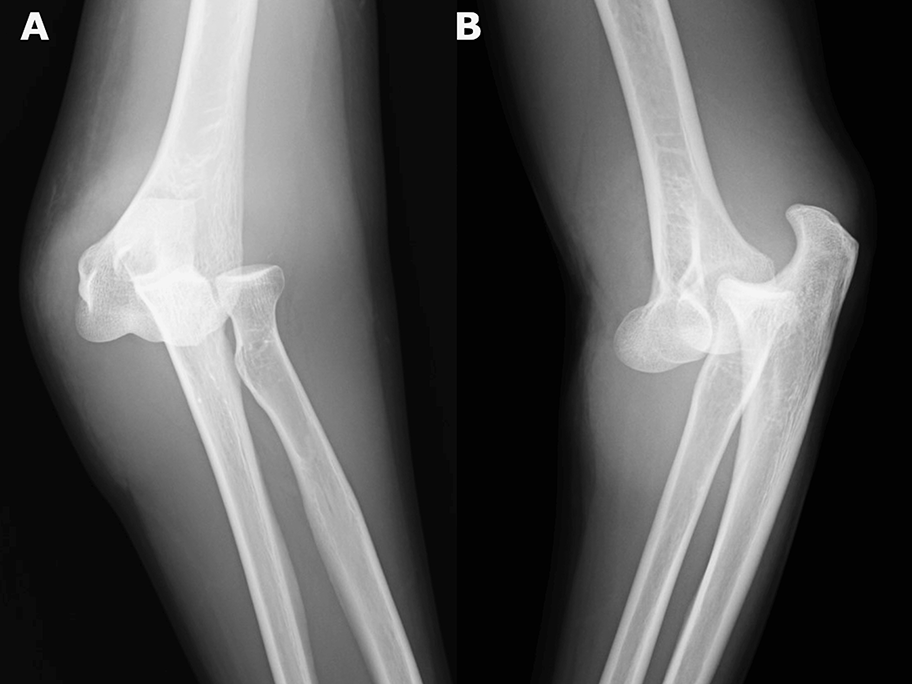

Medical Must-See: How a simple elbow dislocation led to fasciotomy six hours later

A Japanese woman escaped serious complications, including myonecrosis, following a simple elbow dislocation that morphed into acute compartment syndrome, doctors report. The case also highlights…